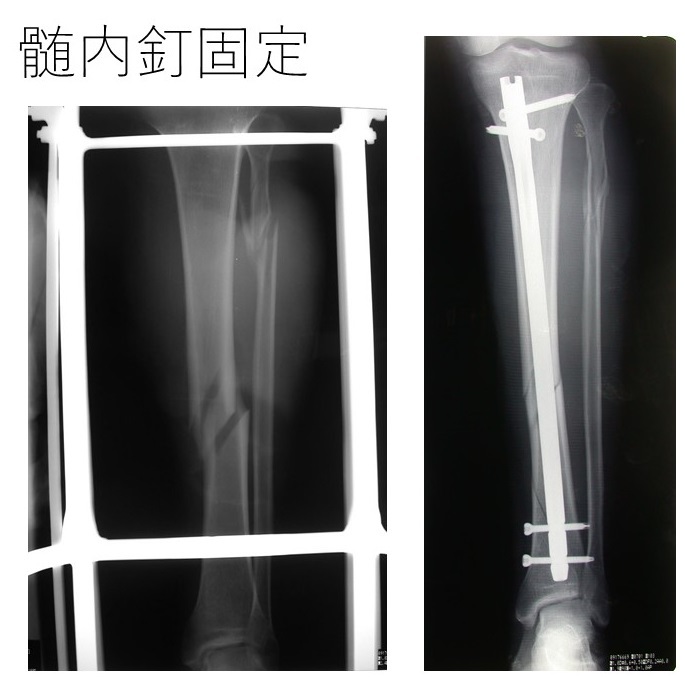

たとえば、大腿骨やスネの骨の骨折時には、「髄内釘(ずいないてい)」という棒状のインプラントを膝部分から挿入する手術法がとられることが増えています。髄内釘手術では、幹部には切開を加えません。

(下腿骨骨折と髄内釘による固定の様子 症例写真提供:須田康文先生)

また、大腿骨、下腿骨、前腕骨や上腕骨骨折などでは、患部を開かず皮膚下に「ロッキングプレート」を沿わせてネジで固定する手術法も用いられています。こういった技術の進歩により、元々骨のつきが悪い部分でも、侵襲性の低い手術で素早い骨癒合を目指すことのできるようになったのです。